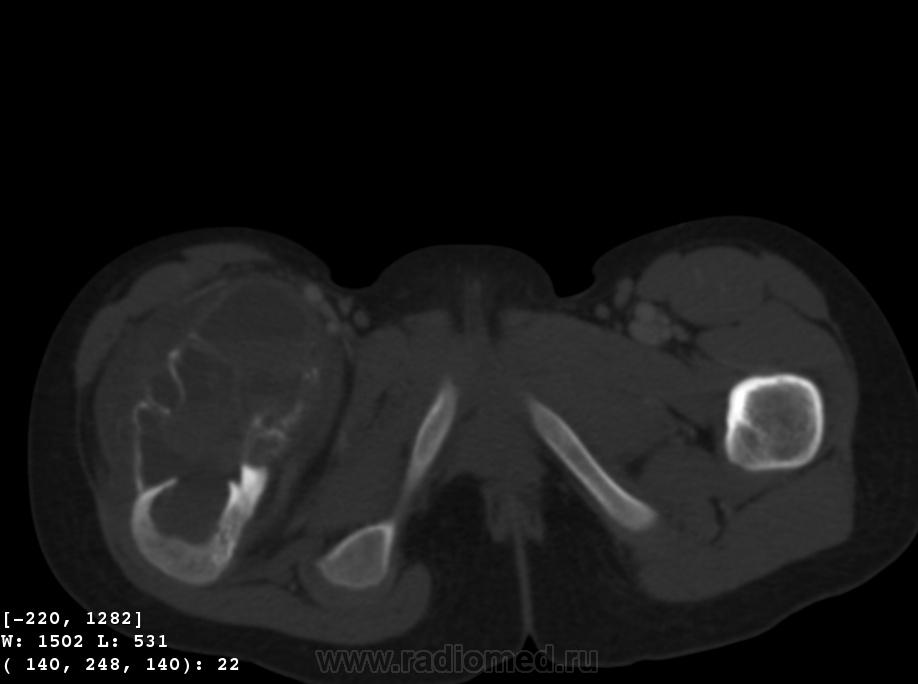

Девочка 9 лет. Родители отмечают, что 2 месяца назад девочка начала предъявлять жалобы на боли в правой пятке. Обследовались, патологии в стопе не нашли. Ребёнок постепенно начал хромать. А несколько дней назад обнаружили припухлость в в/3 бедра. Болей в бедре нет, как ночных, так и дневных. Температура не повышалась. Обратились за помощью - выполнены рентгенограммы, затем - КТ.

Коллеги, давайте правильно применять термины. Периостит - окончание воспаления, применяется при остеомиелите. При опухоли - периостоз - окончание избытка, продуктивного процесса. Здесь есть "козырек Кодмена", спикулообразный периостоз, но есть так же луковичный (слоистый) периостоз, который хорошо виден на отдельных КТ-срезах. Другое дело, что для диф. диагноза опухоли (то что процесс агрессивный - сомнений не вызывыает) это, по большому счету, ничего не дает. Однако, обратите внимание на вздутие. Считаю возможны варианты телеангиоэктатической или гигантоклеточной остеосаркомы. Так же не считаю возможным исключить саркому Юинга.

+ Не потому ,что не согласен с остальными,просто не хочется девчонке "зла " ,а ,кстати на аксиальном срезе -горизонтальные уровни есть ,или это мне кажется ?-Если есть -тогда может быть и впрямь АКК?

Вы правы, коллега, мне тоже видятся уровни. Но если АКК, откуда периостоз? По КТ его оспорить сложно... По скиалогии, локализации наиболее подходит гигантоклеточная опухоль, тем более, что она часто сочетается с вторичной аневризмальной кистой. Но возраст?! хотя, чего сейчас только не бывает...

На операции: прошли фасцию, внешне неизменённые мышцы, обнаружили желтоватую "капсулу" опухоли, после рассечения которой в рану фонтанчиком вылилось около 100 мл гемолизированной крови, а потом разом выкровило около 300 мл свежей. Т.е., как такового мягкотканного компонента опухоли просто не оказалось! Дошли до кости, обнаружили кровоточащий сосуд в канале ближе к шейке бедра. Осуществили гемостаз, на гистологию взяли кусочки "капсулы" и кусочек кости.

Чувства смешанные - с одной стороны, появилась немаленькая надежда на доброкачественность процесса. С другой - неужели АКК и ГКО могут ТАК выглядеть???